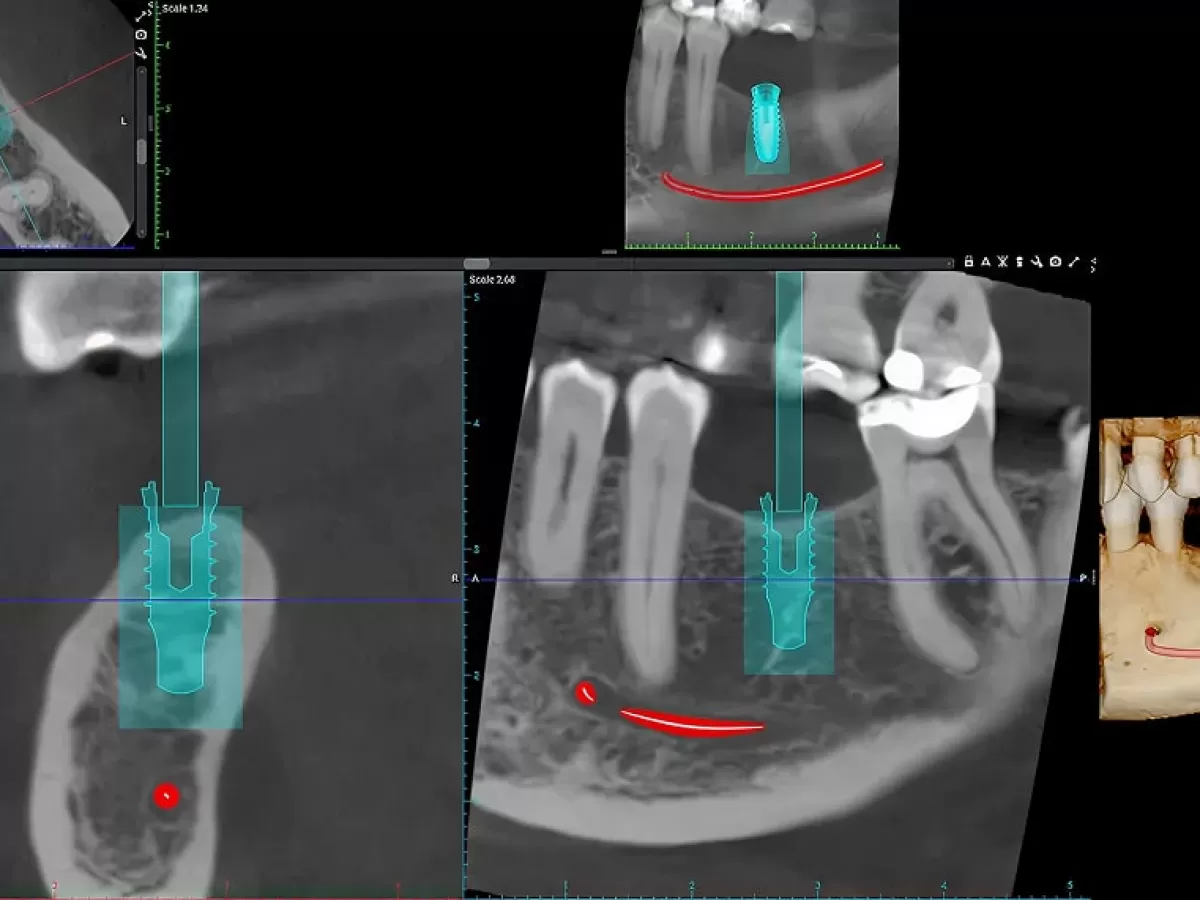

3D скенер и ортопантомограф Planmeca Viso G1 CBCT, който е задвижван от изкуствен интелект и съчетан с Romexis 7.

- Висококачествено 3D, 2D изобразяване – всичко в едно устройство;

- Размери на обеми от Ø 3x3 см до Ø 11x11 см;

- Интуитивно позициониране на пациента и избор на FOV размери на заснемане за оптимална визуализация при минимизиране облъчването на останалите зони;

- Технология за ултраниска доза и патентовани алгоритми за оптимизация;

- Ендо режим с висока резолюция и подобрение, базирано на изкуствен интелект;

- Обширен набор от инструменти за всички дентални специалности;